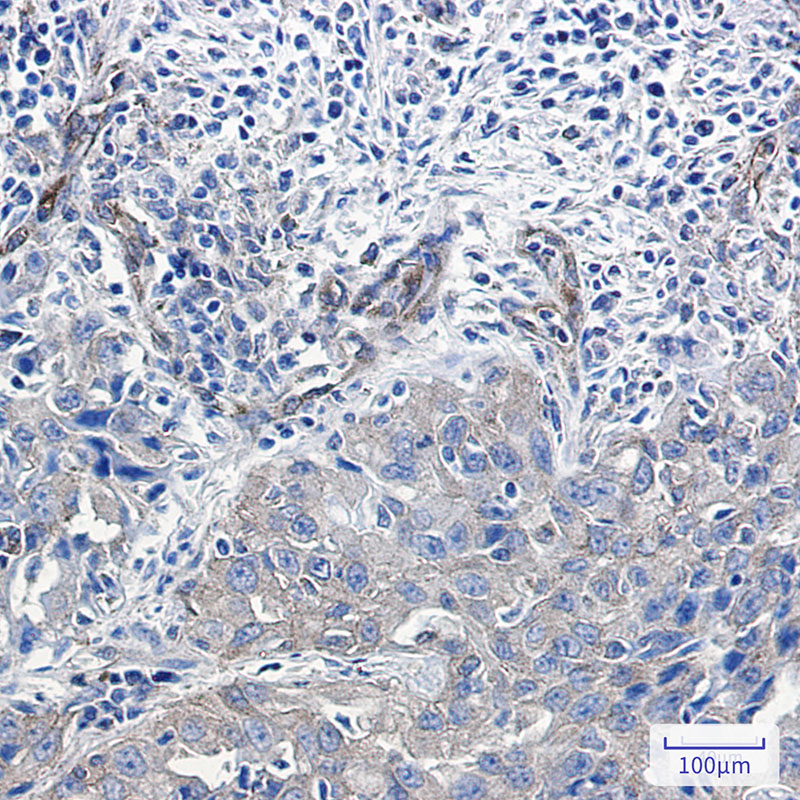

Immunohistochemistry analysis of paraffin-embedded Human lung cancer using NUMB antibody.High-pressure and temperature Sodium Citrate pH 6.0 was used for antigen retrieval.